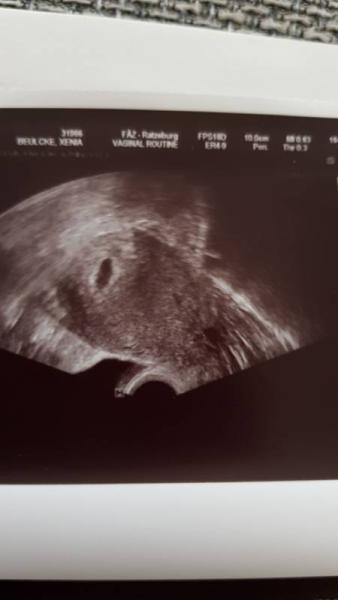

So komme grade von fa. Für die 6 ssw sieht alles gut aus. Man sieht halt noch nich wirklich viel, aber der fa hat mir nochmal bestätigt das das ziehen halt bei einigen stärker is und normal wäre. Nehme jetzt elevit 1 weil die in der Apotheke mir das empfohlen hat. Nimmt das noch jemand?

Bild zu Grade ersten FA Termin hinter mir - Forum für Januar - Mamis